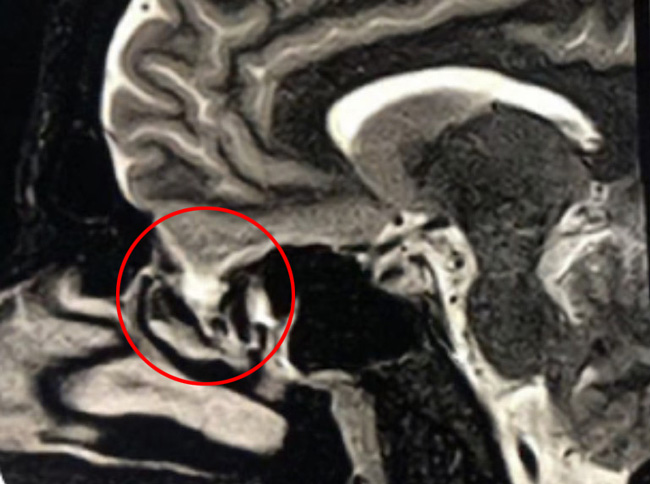

This is a 39 year old physician with a long history of sinus issues, who more recently had noted an increased drainage of clear fluid from his nose. Testing of the fluid for Beta-2-transferrin demonstrated that it was consistent with cerebrospinal fluid (csf). MRI and CT scan demonstrated an encephalocele in the frontal most part of the anterior skull base, on the left, just off midline (Figures 1a,1b,1c). For the last 3 weeks, he has also been having headaches and neck pain.

Figure 1a – Coronal CT bone window

Figure 1c – Sagittal T2 MRI